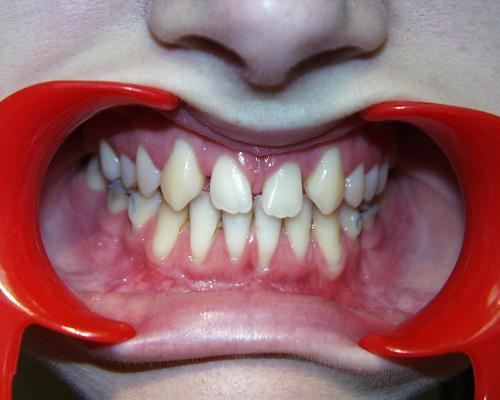

Nach der Behandlung

(Dauer der aktiven Behandlung: 1 Jahr, 11 Monate)

Die seitlichen Schneidezähne wurden nach Beendigung der aktiven Behandlung vom Hauszahnarzt mit laborgefertigten Keramik-Verblendschalen, sog. Veneers, verbreitert, die Eckzähne mit plastischem zahnfarbenem Füllungsmaterial und Beschleifen zu Schneidezähnen umgestaltet. Bei den im Unterkiefer ausgleichend entfernten beiden Zähnen handelte es sich um Milchbackenzähne, die keine bleibenden Nachfolger hatten. Auch diese Lücken wurden allmählich geschlossen, so daß die Seitenzahnreihen anschließend gut aufeinander paßten.